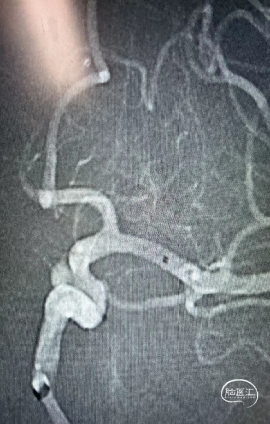

术后即刻影像及患者术后情况

最终正侧位造影见载瘤动脉通畅,动脉瘤完全不显影,远端血管显影良好。

充分评估是前提,根据手术路径,制定合理的手术方案,选择适合的通路产品。术中关键器械的选择:Skathi远端通路导管和Locaste输送导管搭配,既为近端提供强劲支撑性,又使微导管到位后,填塞动脉瘤过程中增加稳定性。为手术安全顺利结束保驾护航。